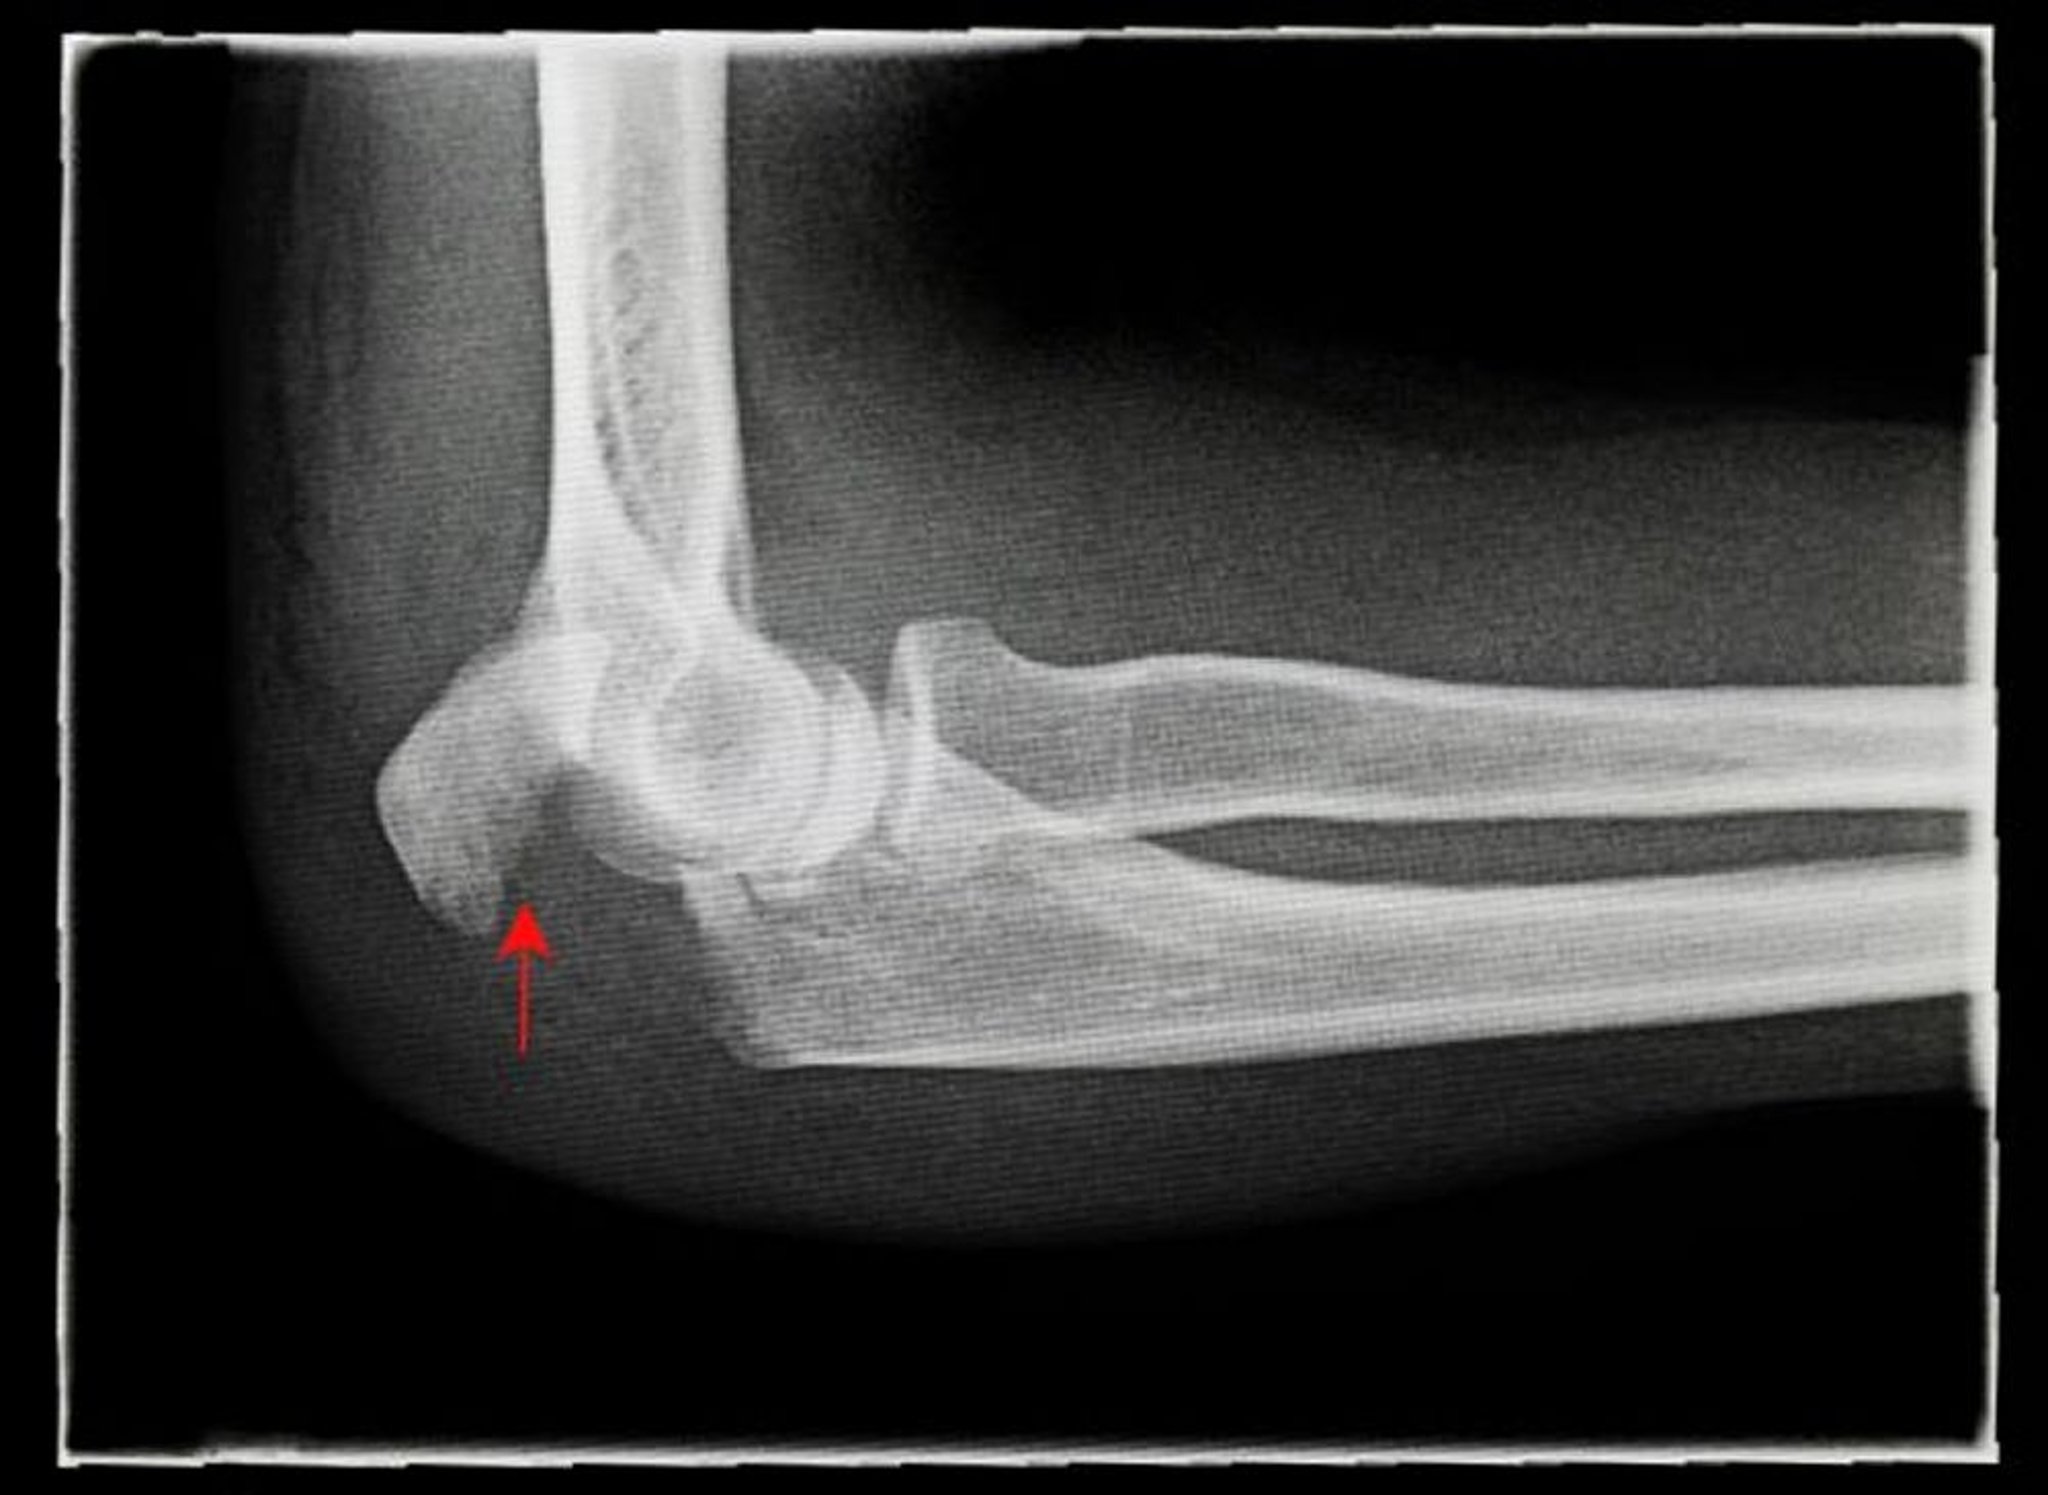

Frattura dell'olecrano

Questa radiografia di profilo mostra una frattura scomposta dell'olecrano (freccia).